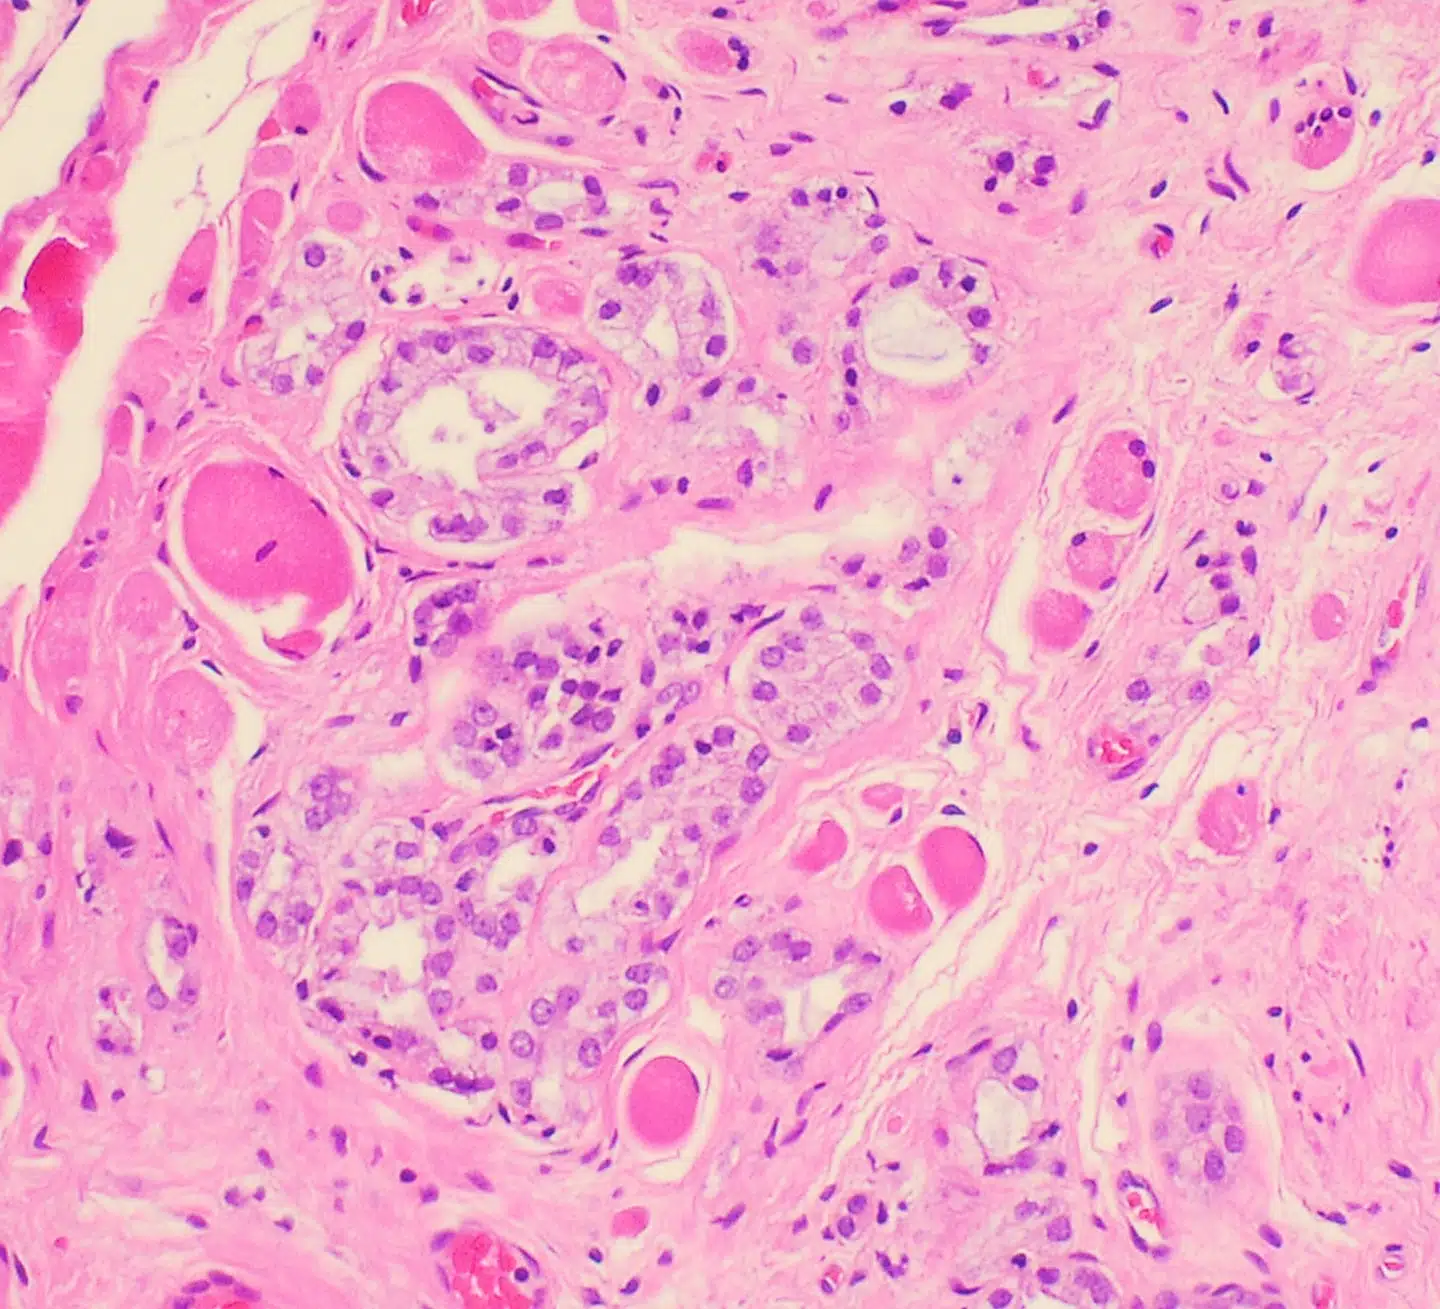

Omkring halvdelen af alle 50-årige mænd har kræftceller i prostata, blærehalskirtlen, der sidder under urinblæren, mens det er tilfældet for omkring 75 procent af alle 75-årige mænd, viser tal fra Prostatakræftforeningen. Det er dog langtfra alle cellerne, som er aggressive eller spreder sig til resten af kroppen. Når læger opdager tidlige celleforandringer eller mutationer i prostata, diagnosticerer de patienterne med kræft.

Men nu argumenterer tre forskere i en artikel i Journal of the National Cancer Institute for, at den praksis skal stoppes. For i visse tilfælde af såkaldt low grade cancer kaldet GG1, hvor kræftcellerne er få og ikke har muteret, sker det kun sjældent, at cellerne bliver aggressive eller spreder sig.

I artiklen lyder det fra forskerne, at en navneændring af GG1-stadiet vil få positive effekter for patienter, da en kræftdiagnose giver forøget risiko for sundhedsskadelig overbehandling, ligesom den har store konsekvenser for patientens mentale helbred, da mange forbinder kræft med et slemt sygdomsforløb eller død. Tilstanden er let at opdage og behandle og kan derfor med fordel omdøbes, vurderer forskerne. De foreslår, at GG1 i stedet skal kaldes et »incidentalom«, som er en asymptomatisk tumor.